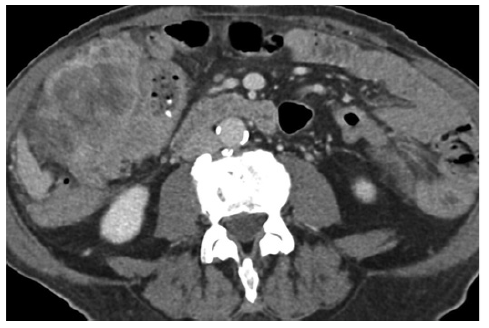

Diagnostic work-up, including a computed tomography scan and colonoscopy, revealed a large neoplasm in the cecum/ileocecal valve region, extending into the terminal ileum and ascending colon (Fig. 3). Histological analysis confirmed adenocarcinoma, staged as a cT4aN2M0.

Fig. 3. Computed tomography (CT) showing neoplasia of the cecum/ileocecal valve region with transmural infiltration.